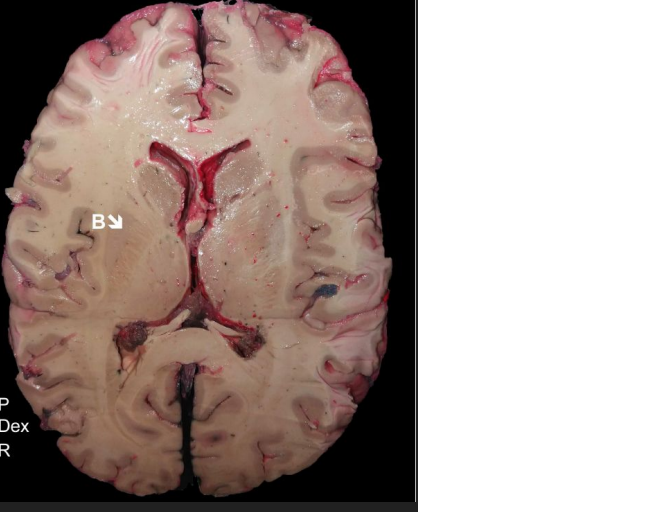

nucleus caudatus dex.

nucleus lentiformis dex.

capsula interna sin.

ventriculus lateralis dex.

septum pellucidum

Insula Dex.

lobus frontalis dex.

lobus occipitalis sin.

fissura longitudinalis cerebri

ventriculus III

komora III